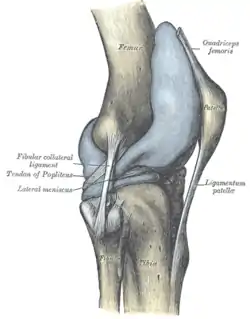

Knee from the side, with lateral meniscus simply labeled as "meniscus". | |

The lateral meniscus is grooved laterally for the tendon of the popliteus, which separates it from the fibular collateral ligament.

Right knee-joint, from the front, showing interior ligaments. Capsule of right knee-joint (distended). Lateral aspect.

Capsule of right knee-joint (distended). Lateral aspect. Capsule of right knee-joint (distended). Posterior aspect.